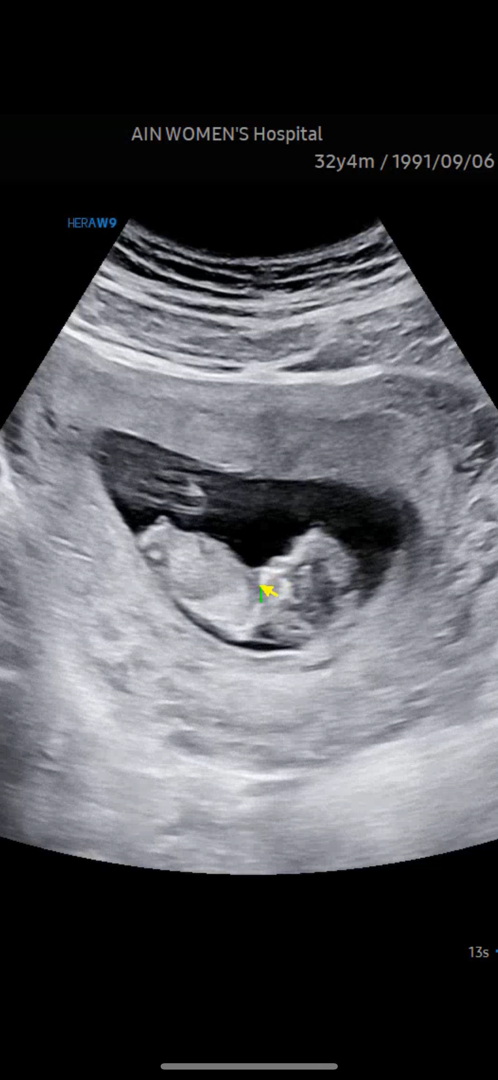

11주 사진으로 각도법

11주 2일차로 찍은 촘파인데 각도법 될까요?ㅎㅎㅎ 저는 딸, 남편은 아들 원하는데 이르지만 궁금해서 다른 분들 조언 얻어보려고 올려봐요~!ㅎㅎ

아들에 한표요 ^^

제가 본 그게 꼬튜가 맞다면 각도법 상 아들인 것 같어요! ㅎㅎㅎ 맞는지 나중에 알려주게요~